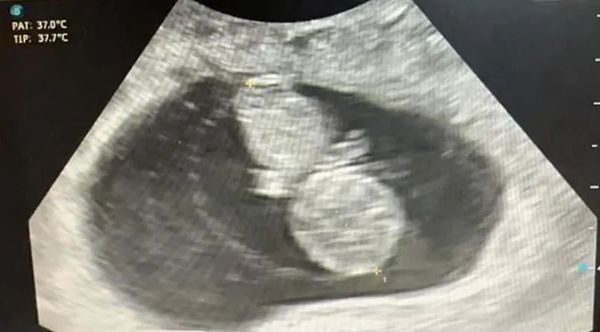

时隔2年,2024年1月,小菊重新回深圳中山妇产医院接二胎宝宝,经过耿妈妈综合评估符合移植条件,遂复苏冷冻移植1个囊胚,顺利验得好孕,成功通过三超“毕业”。